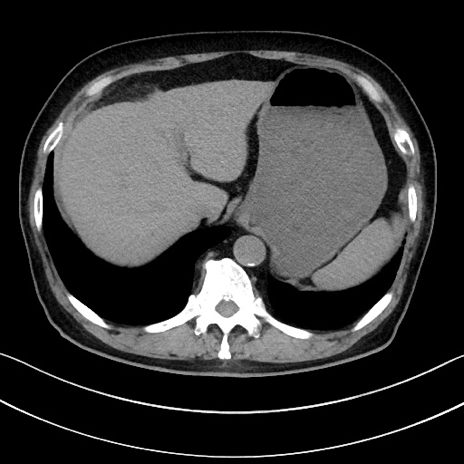

冠状断像

【症例】70歳代男性

【主訴】腹痛

【現病歴】今朝から腹痛あり。全体的に痛い。特に左上の方。排ガスが今日はない。冷や汗が出る。

【既往歴】直腸癌術後

【身体所見】左側腹部〜上腹部に圧痛あり。腹膜刺激症状明らかなではない。軽度反跳痛。左下腹部に術後瘢痕あり。

【データ】WBC 7700、CRP 0.02